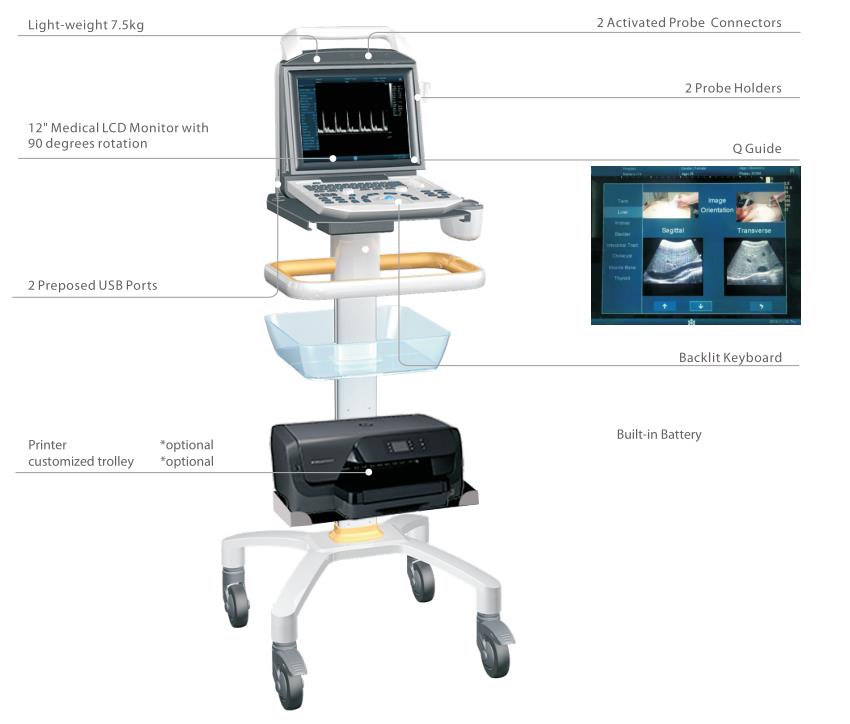

ZONCARE Medical Ultrasound Instruments Outstanding Portable Veterinary Ultrasound Scanner for Animals

Specification

item | value |

Model | ZONCARE-i50 |

AC adapter Input | Voltage: 100-240V~ Frequency: 50/60Hz Power Consumption: 320VA |

Built-in Battery | Lithium-ion rechargeable battery: 18650/6200mAh/66.9Wh Nominal voltage: 10.8V Limited charging voltage: 12.6V |

Imaging mode | B, 2B/4B, M, B/M, PW |

Display | 12 inch color display screen |

Transducer ports and holders | 2 transducer ports 2 removable transducer holders |

Clinical Applications | Abdomen, Obstetrics, Gynecology, Urology, Cardiology, Small Parts, Blood Vessel, Superficial, Thyroid, Galactophore, Custom |

Resolution | 1024 *768 |

Tile Angle | 0-90° |

Voltage | 100-240V~ |

Frequency | 50/60Hz |

Gain | Adjust the whole image gain value |

Save | Save image/report |

Transducer Types | Convex transducer, Linear array, Trans-vaginal transducer, Micro-convex transducer |

Operation Environment | Ambient temperature: 5 ℃~+40℃ Relative humidity: 25%~85% Atmospheric pressure: 700hPa~1060hPa |

Storage &Transport Environment | Ambient temperature: -20 ℃~+55℃ Relative humidity: 10%~95% Atmospheric pressure: 500hPa~1060hPa |

Support Language | Chinese, English, Spanish, French |

Net Weight | 6.2 kg |

Dimension | 37*36*15.5 cm |

Product Features

Features

●12-inch high resolution medical LCD monitor● Two transducer connectors● Auto-freezing function● Auto-generation BMP format report● Full screen imaging FSI● Q-Guide ● One key data storage● Multiple data transmission● Optional USB foot switch● Optional built-in battery● Optional customized trolley and suitcase● Transducers: Convex, Linear, Transvaginal, Micro-Convex

Advanced Imaging Technologies

* One Touch Optimization

* Speckle Noise Reduction Imaging

* Tissue Harmonics Imaging

* Tissue Specific Imaging* PW Mode